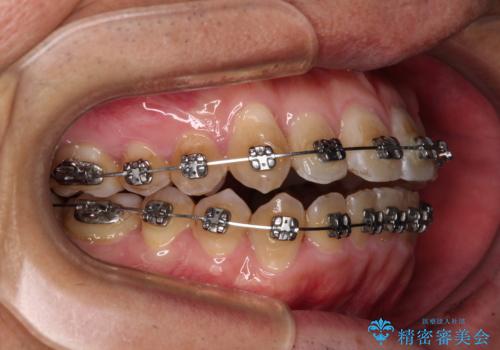

治療終了直後は上下前歯が接触していましたが、舌の突出癖がなかなか改善されず、終了時の口腔内写真撮影時には、既に上下前歯に隙間ができてしまいました。